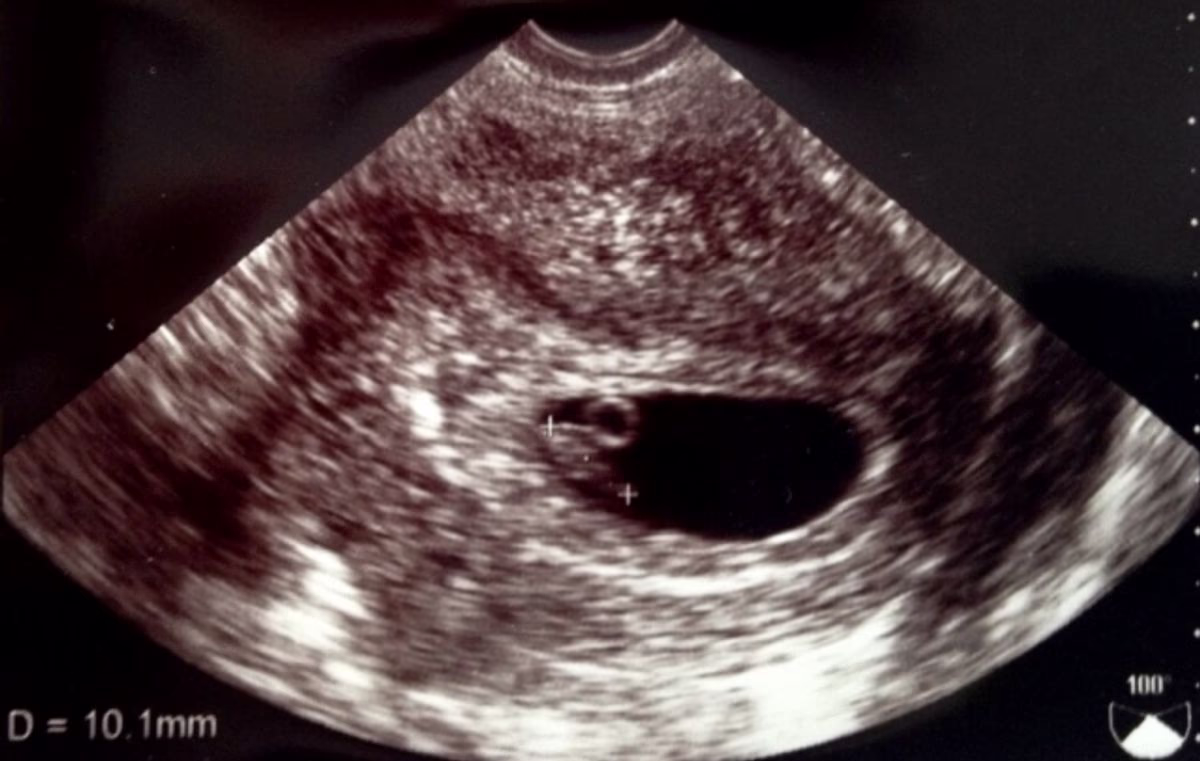

そして、流産のほとんどは妊娠初期、特に妊娠12週までに起こることが多く、全体の約8割を占めています。

妊婦健診は、赤ちゃんの発育状態やママの体の変化をチェックする大切な機会です。定期的に妊婦健診を受けましょう。